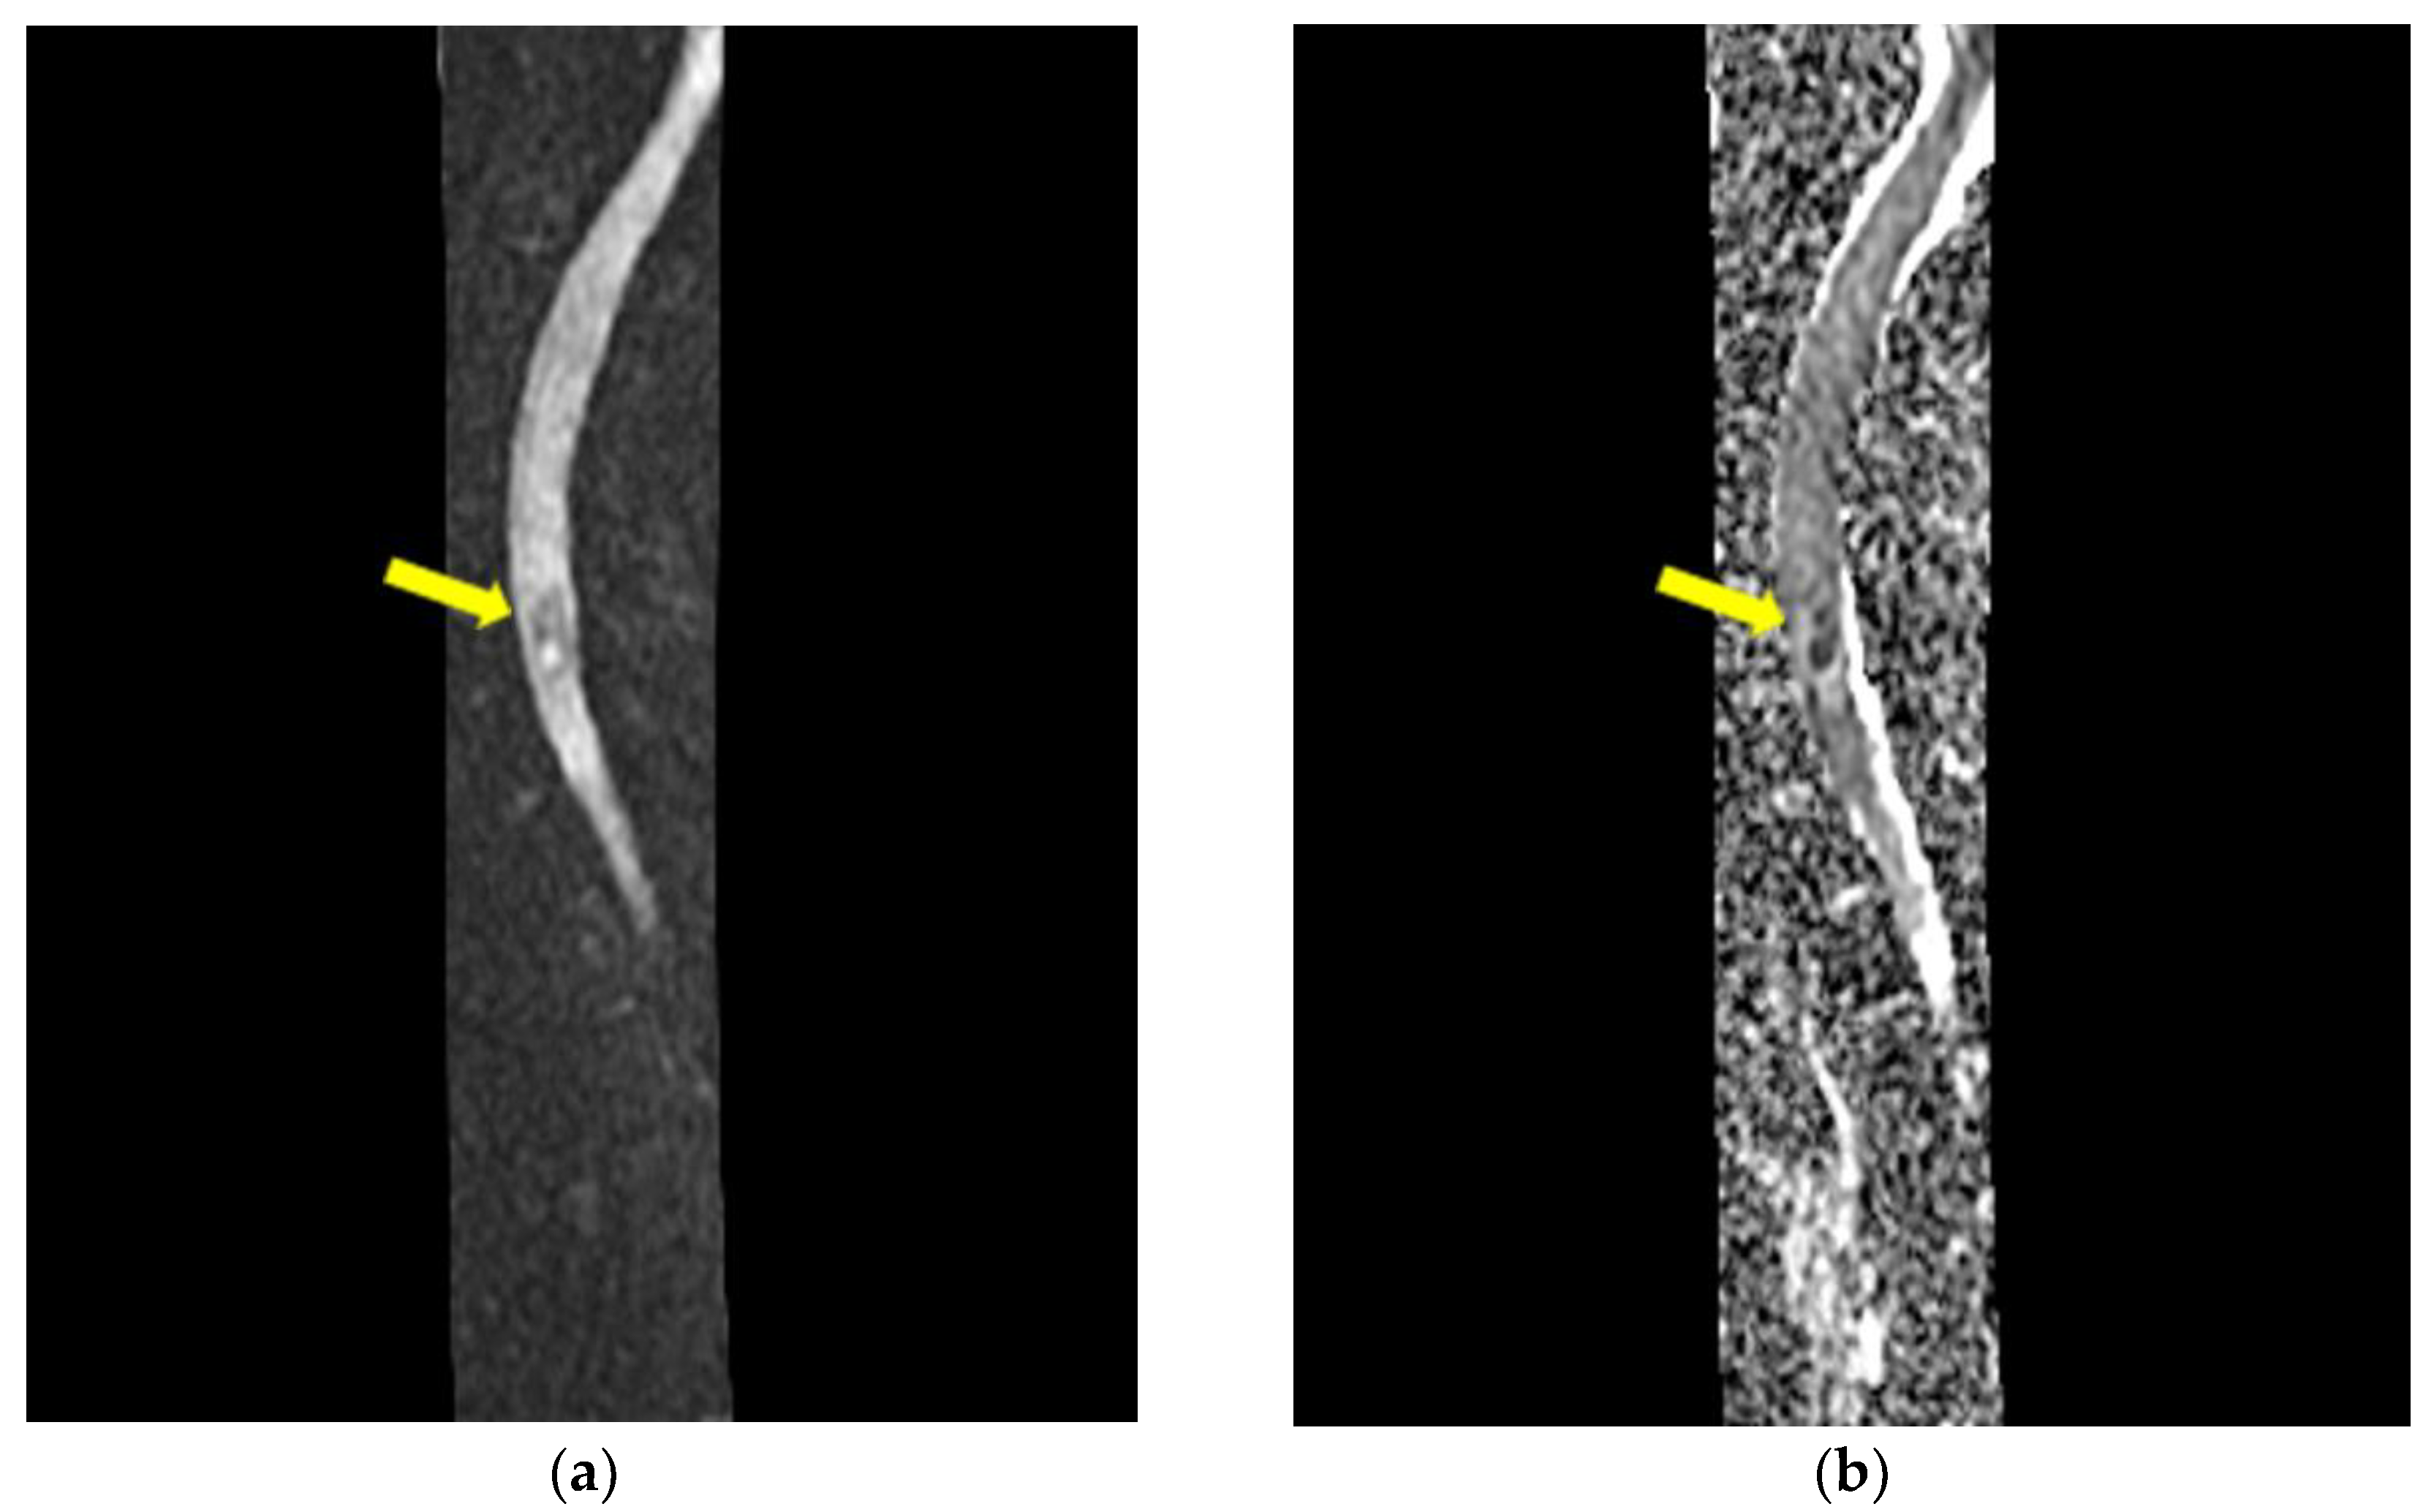

- Mycological demonstration of Aspergillus fumigates hyphae by microscopy from spu-tum, microscopy and culture from bronchial aspirate, and histopathological evi-dence of the presence of Aspergillus fumigates hyphae with dichotomous branching in the spinal cord biopsy;